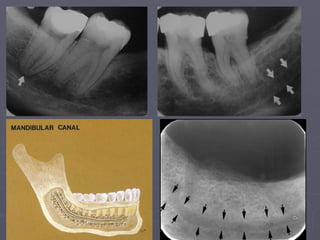

Mandibular canal

► It is a dark linear shadow with thin radiopaque

superior and inferior borders.

► Sometimes the borders are seen only partially

or not at all.

► The relationship of the canal to the roots of

the lower teeth may vary.

► If projected over the root apices, the lamina

dura will be overexposed and misinterpretation may

occur.

Nutrient canals :

The arrows above

identify nutrient

Canals.

They are most often seen

in

Persons with thin bone

and in

Those with high blood

pressure

Or advanced

periodontitis.

Nutrient canals

Mandibular canal ► Itis a dark linear shadow with thin radiopaque superior and inferior borders. ► Sometimes the borders are seen only partially or not at all. ► The relationship of the canal to the roots of the lower teeth may vary. ► If projected over the root apices, the lamina dura will be overexposed and misinterpretation may occur.